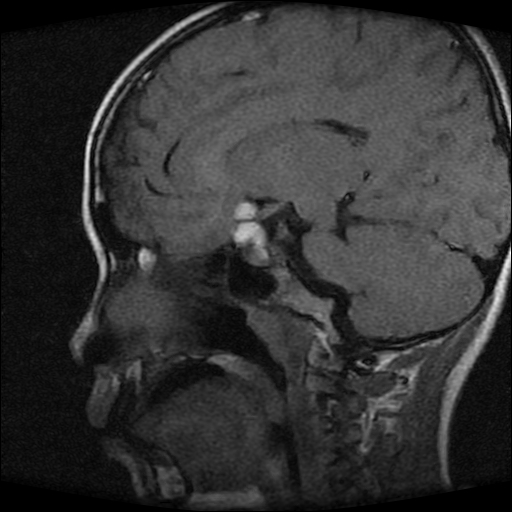

男性,12岁。反复头痛呕吐半月。脑积液无异常。病变部位ct值32hu,dwi无异常。

鞍上为主,累及鞍内,垂体受压位于鞍底。mri呈短t1、长t2信号,不太支持生殖细胞肿瘤,首考颅咽管瘤。

鞍内囊性占位性病变,t1wi、t2wi,均为高信号影。ct平扫为等密度。发病年龄较小。故首先考虑颅咽管瘤,可以做ct增强扫描

鞍内囊性占位性病变,t1wi、t2wi,均为高信号影。ct平扫为等密度。发病年龄较小。故首先考虑颅咽管瘤。